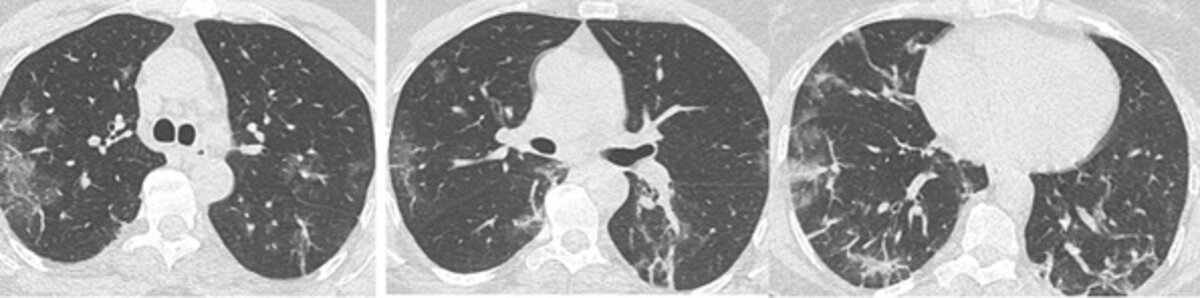

Le scanner est en effet l’examen le plus sensible dans le cadre de la détection diagnostique du virus. En tout cas il l’est largement plus que le prélèvement par écouvillonnage nasal qui donne des statistiques de 30% de faux négatifs. Il est aussi plus que le prélèvement sanguin. Les images typiques de « plages et nodules de verre dépoli à prédominance sous pleurales *» sont souvent significatives !

Ces images se retrouvent pour les patients dont les symptômes sont apparus depuis plus de 2 jours (en deçà, 56% des scanner sont normaux). Il faut bien sûr établir un diagnostic différentiel et éviter la confusion avec les images d’embolies pulmonaires à faible lésions parenchymateuses, mais aussi ne pas confondre avec certaines formes de myocardites. La sensibilité du scanner couplée au suivi radiodiagnostic des patients Covid + jette un focus sur notre job et donne un relief inattendu à notre activité professionnelle.